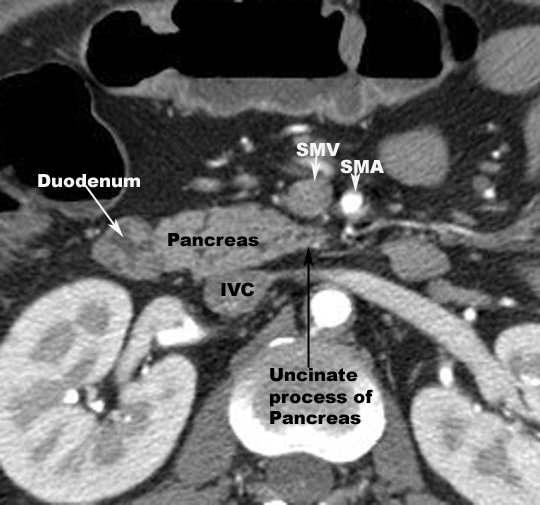

- Head

- Posterior

- SMV

- Splenic vein

- IVC

- Terminal portion of renal vein

- Uncinate process passes in front

of Aorta